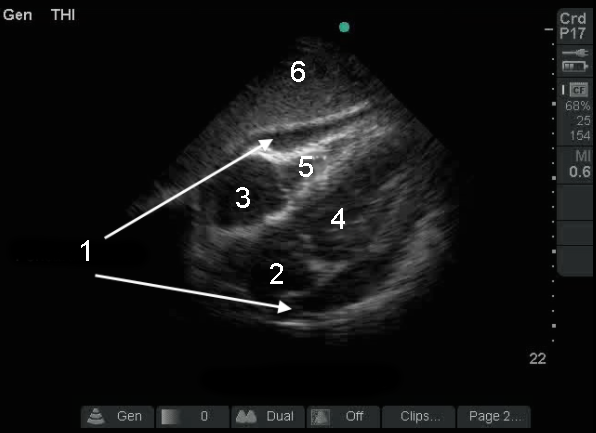

心剣状突起下心嚢液画像

心膜液(滲出液)

左心房(LA)

右心房 (RA)

左心室(LV)

右心室 (RV)

肝臓